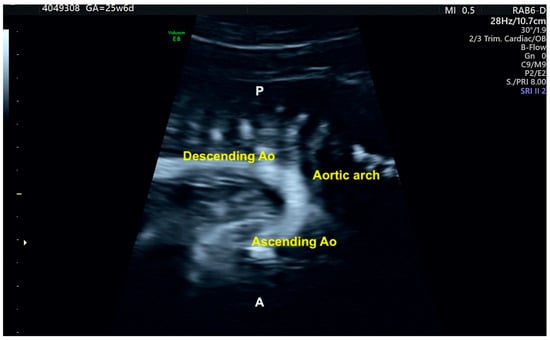

To obtain a cardiac volume using the STIC method, the examiner must obtain a 4C view of the fetal heart, whenever possible, with the fetal spine positioned as close to 6 o’clock as possible. Ideally, this image acquisition should be performed with the pregnant woman in apnea for a few seconds and the fetus at rest. The settings for this acquisition are: an opening angle between 20° and 40° and an acquisition time between 7.5 and 15 s according the gestational age [17]. By adjusting the brightness and color, STIC in the rendering mode allows the detailed evaluation of cardiac anatomy and measurement (area and volume) of a variety of structures of the fetal heart, such as the interventricular septum, valves, and papillary muscles [18,19,20,21,22]. STIC technology can reconstruct moving images and display them in grayscale, Doppler mode (inversion mode/color Doppler), B-flow imaging, and Tomographic Ultrasound Imaging (TUI) [23,24,25,26] (Figure 4, Figure 5 and Figure 6).

Figure 5.

Aortic arch imaging using B-flow Imaging with Spatiotemporal Image Correlation method on fetus with normal heart. This technique encodes the blood signal and provides high-quality images similar to aortic angiography. Ao: aorta; P: posterior; A: anterior.

Grayscale STIC allows the assessment of the ventricular outflow tracts as well as the aortic and ductal arches. In this scenario, the B-flow imaging technique in STIC enhances the weak signals from blood and eliminates strong signals from nearby structures and is potentially superior to color Doppler in the assessment of large vessels and venous connections. B-flow imaging produces images similar to angiographic images (Figure 5 and Video S1). The post-processing inversion mode (inverted flow) is another technique that analyzes fluid structures and inverts the grayscale voxels. The inversion mode allows the reconstruction of ventricles, aortic, and ductal arches, as well as abnormal venous connections and septal defects (Figure 6 and Video S2).